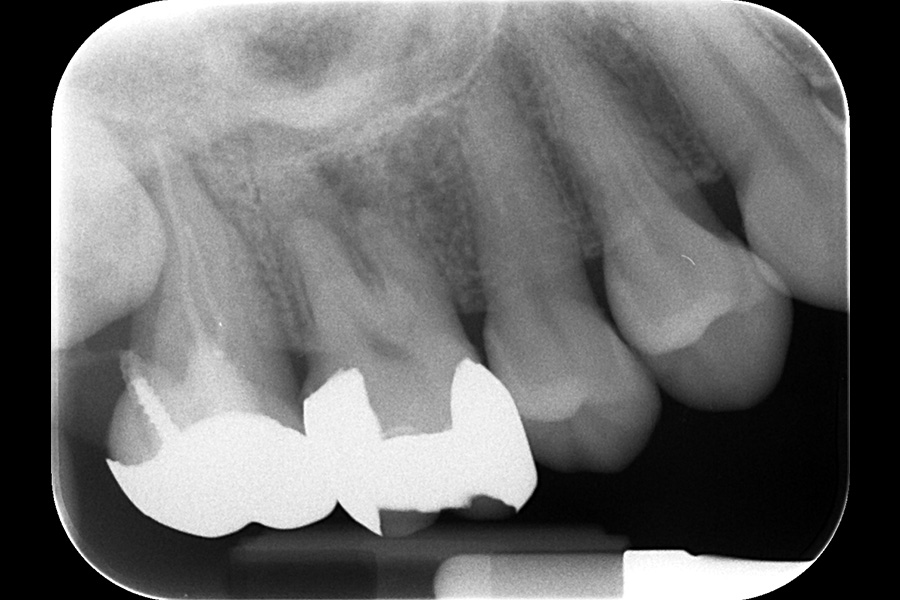

治療後